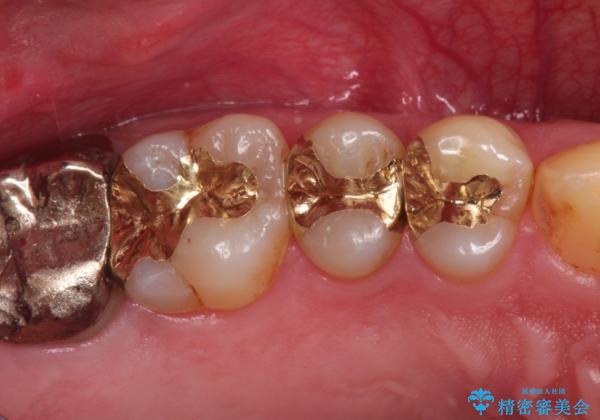

精密なむし歯の治療 ゴールドインレー

- 定期健診にてむし歯を認めたためゴールドインレーにて治療を行いました。

ゴールドインレーは適合が良く、割れることもないため、長期的に安定した治療法となります。